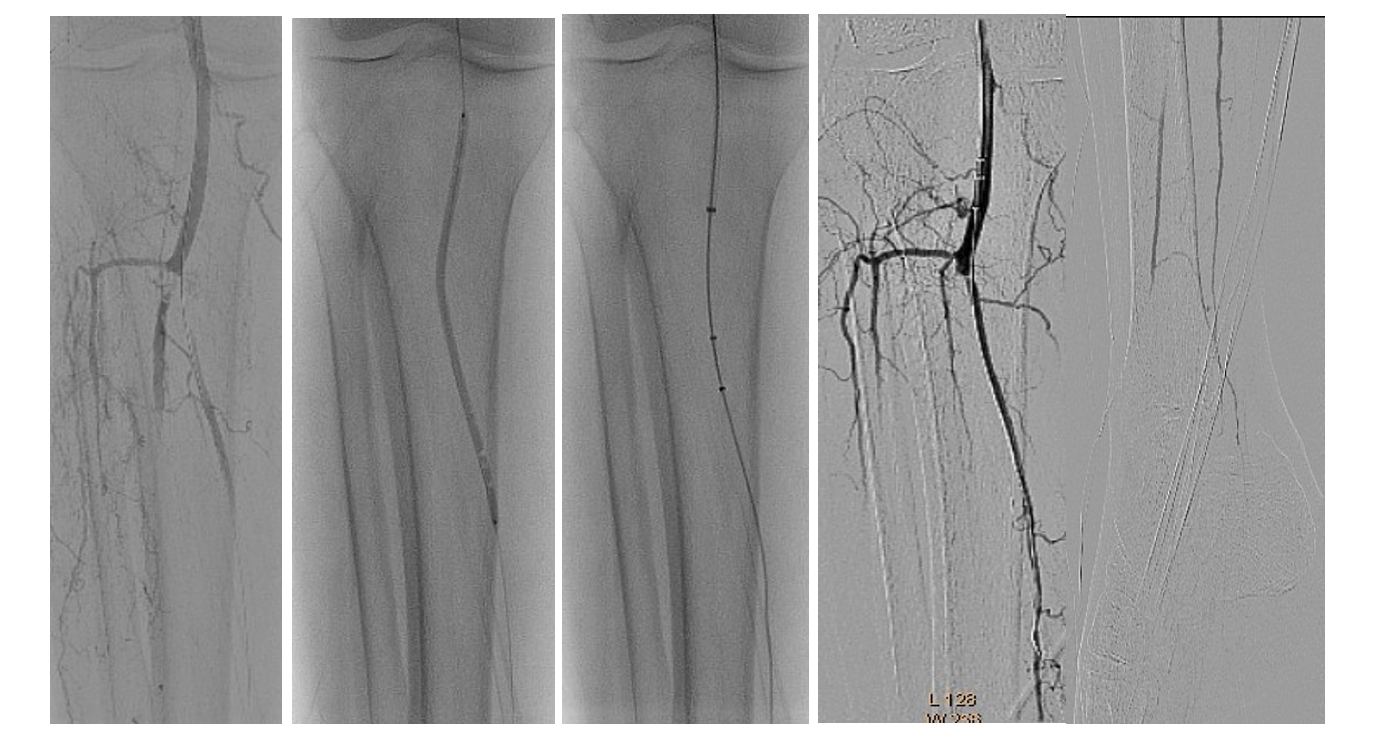

The diagnostic catheterization of the right lower extremity showed a “riding” thrombus at the bifurcation of the superficial femoral artery (SFA)/profunda femoris artery (PFA) and a long thrombotic occlusion starting from the middle segment of the SFA involving the popliteal artery and tibiofibular trunk (Figure 2). In the setting of simultaneous acute limb ischemia (ALI) of the right upper and lower limbs, we performed ad hoc concomitant percutaneous transluminal thrombectomy (PTA).

The same introducer was redirected with the tip in the right common femoral artery. PTA of the right SFA, PFA, and popliteal and posterior tibial arteries was performed. Recanalization with a 0.035" Stiff Glidewire (Terumo) and a NaviCross Support Catheter (Terumo). The “riding” thrombus at the SFA/PFA bifurcation then migrated distally and occluded the SFA and PFA (Figure 8). We began EVT from the proximal segment of the SFA, with the same 2.06 mm AngioJet Solent Omni catheter. EVT was performed in the middle segment of the SFA and the popliteal artery (Figure 9). Due to residual thrombosis in the distal segment of the SFA, a balloon dilatation with a 5/120 mm Armada catheter (Abbott) was done (Figure 10).